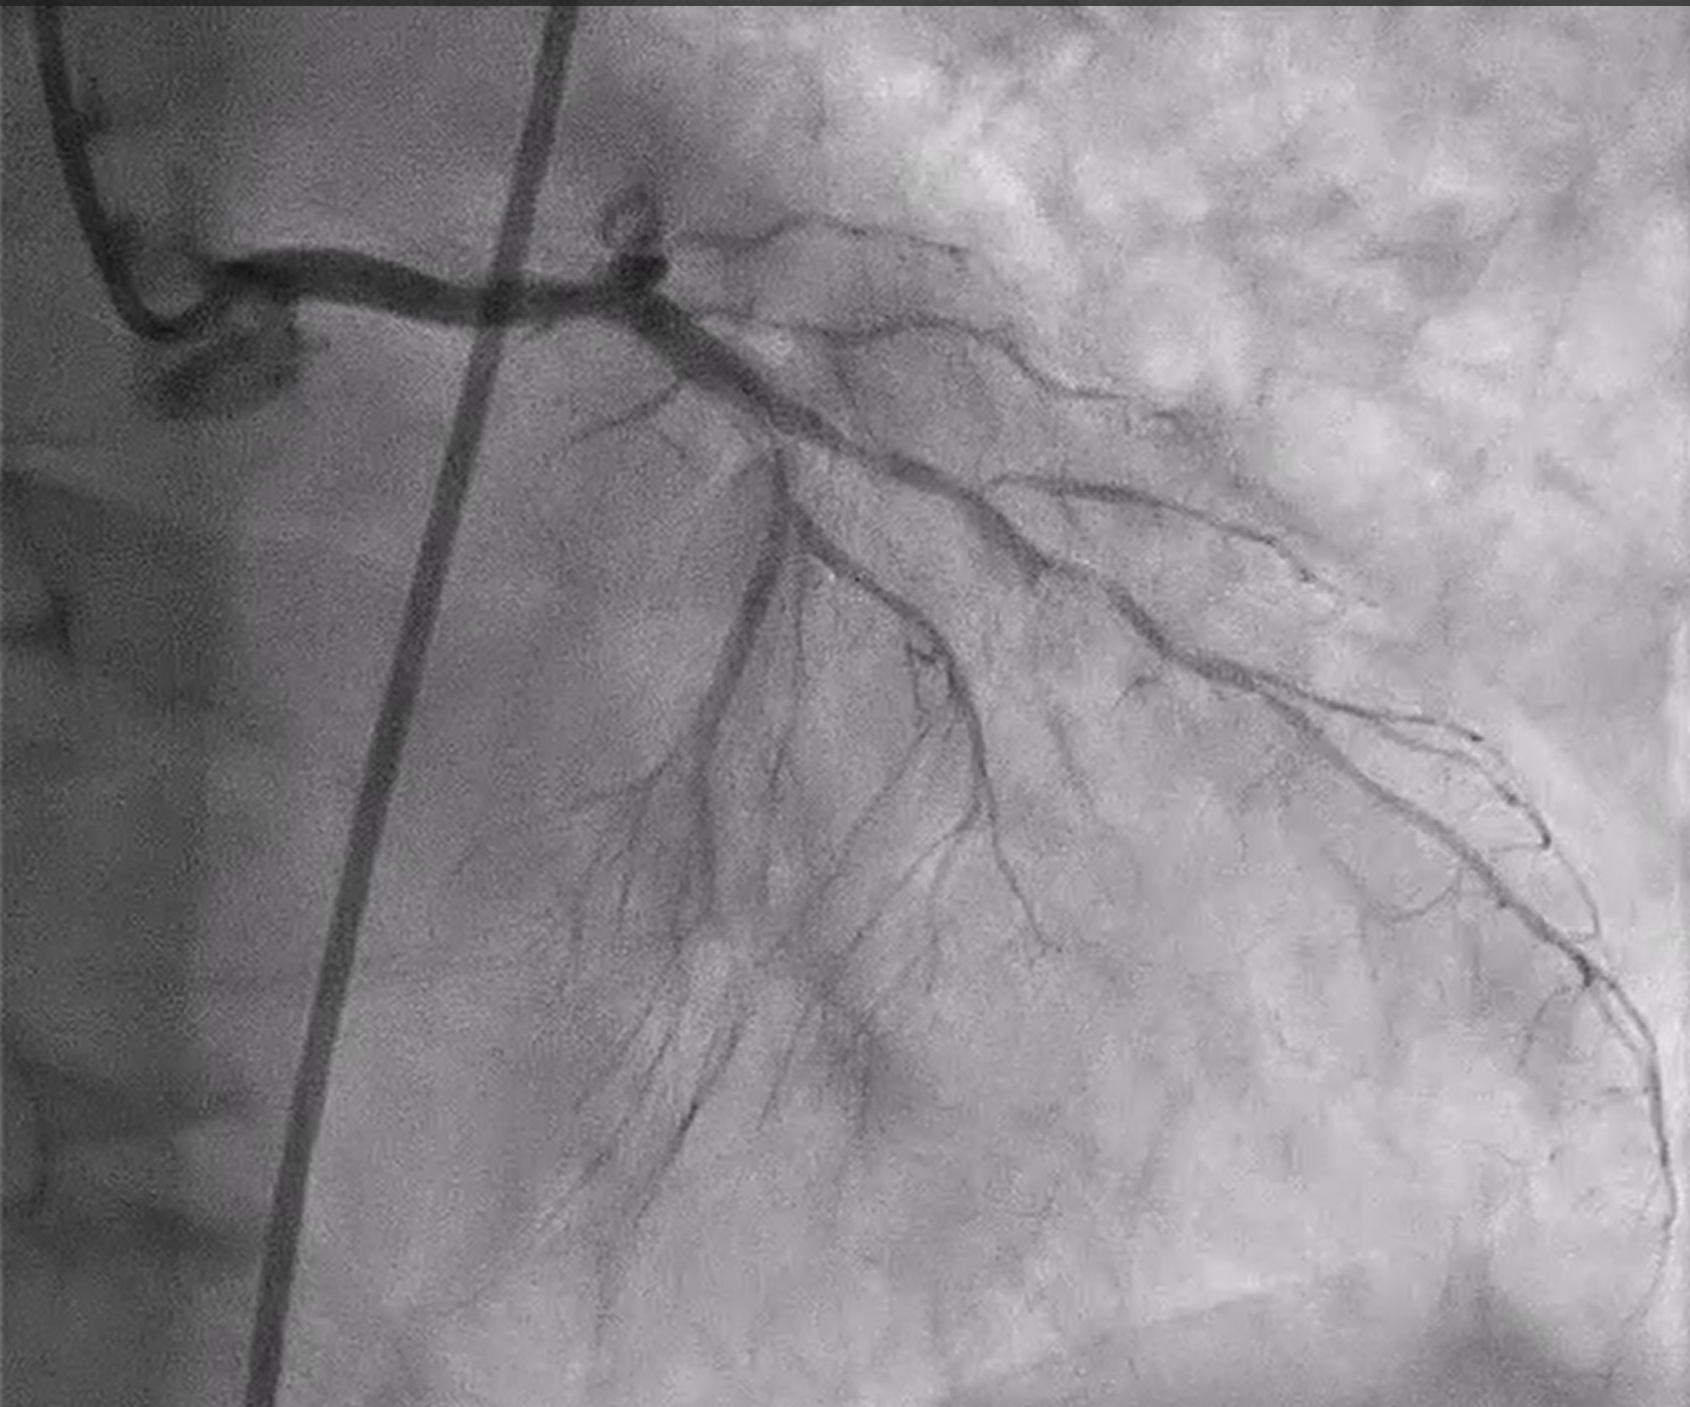

Coronary angiography revealed heavily calcified along LM, proximal to mid LAD, LCx and proximal RCA. 50% stenosis at distal LM bifurcation (Medina 1-1-0). 70% stenosis at proximal LAD and total occlusion at mid LAD. Total occlusion at proximal LCx. No significant stenosis of RCA. There were collateral circulations from septal branch of LAD to distal LAD and from PL to distal LAD and distal LCx.

We performed PCI at CTO LAD and LCx with contralateral injection with antegrade wiring and upfront rotablation at LM, LAD and LCx due to heavily calcified lesion. The 7 Fr EBU 3.5 and 6 Fr JR 4.0 catheter were engaged into LCA and RCA, respectively. We opened the LCx CTO segment using microcatheter with Fielder XT guidewire (GW) then rewire from LCx to distal LAD. The CTO GW was exchange to RotaWire Floppy. Rotablation was done at LM-mid LAD with Burr 1.5 mm and LM-proximal LCx with Burr 1.5 mm. IVUS showed EEL of mid LAD = 2.5 mm, proximal LAD = 4.0 mm, distal LM = 5.5 mm and proximal LCx = 3.5 mm. The lesion of mid LAD was prepared with scoring balloon 2.0/15 mm and LM-proximal LAD with scoring balloon 3.5/15 mm. A 2.5/33 mm stent was deployed from proximal-mid LAD. We decided to stenting the lesion at proximal LCx before stenting the lesion at LM-proximal LAD using provisional one stent and POT-kiss-POT technique. A 3.0/26 mm stent was deployed at proximal LCx. A 3.5/38 mm stent was deployed from distal LM-proximal LAD and 3.5/13 mm stent from ostial LM-distal LM. POT was done with a non-compliance (NC) 5.0/12 mm balloon along LM stent. Kissing balloon inflation with NC 3.0/15 mm balloon at LM-LCx and 3.5/15 mm balloon at LM-LAD then final POT with NC 5.0/12 mm was done. IVUS showed well stent expansion, no malapposition and no stent edge dissection. The patient had no re-admission. Echocardiography after 3 months showed significant improvement of LV function to 56%.